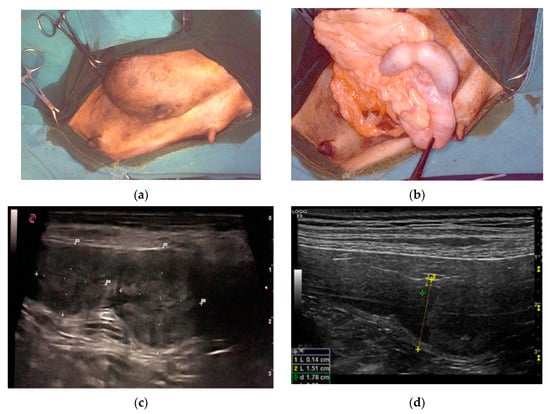

Clinical history of the PEH cases showed one or more episodes of pseudopregnancy (D1, D2) after previous heat. Case D1 showed again pseudopregnancy signs after removal of the genital tract. They were seen in heat 1.5 or 2 months before the admission and were not mated. The female dogs were asymptomatic with blood parameters into the normal ranges. Surgery was done for anticonception purposes (D1, D3, D6). Case D2 presented an inguinal hernia that at surgical correction revealed a uterine content (Figure 1a,b).

Figure 1.

Clinical findings in three different cases of pseudo-placentational endometrial hyperplasia: (a) inguinal hernia with a uterine content in case D2; (b) at the opening of the hernia, the uterus with segmental swelling is evident; (c) ultrasound appearance of the lesion, resembling a placental remnant in case D4; D = distance (d) ultrasound appearance of the lesion in case D5, L= length, D = distance.

Ultrasound showed a focal widening of the uterine horn with two, ovoid, broadly base, pedunculated masses (case D4) protruding from the endometrium and filling most of the lumen. The lesions were heterogeneous in echotexture, slightly hyperechoic, and reminiscent of cerebral convolutions, with well-preserved wall layering (Figure 1c). In case D5, the uterus had a small amount of poorly particulate endoluminal fluid, which was more evident in the cranial part of the right horn, and a parenchymal endoluminal proliferation of about 1.5 × 2 cm in size. It showed an undulating hypoechoic crown with a thickening of 3 mm and an anechoic center (Figure 1d). Based on these findings, PEH was suspected in both cases. Lacking reproductive interest, ovariohysterectomy was performed.